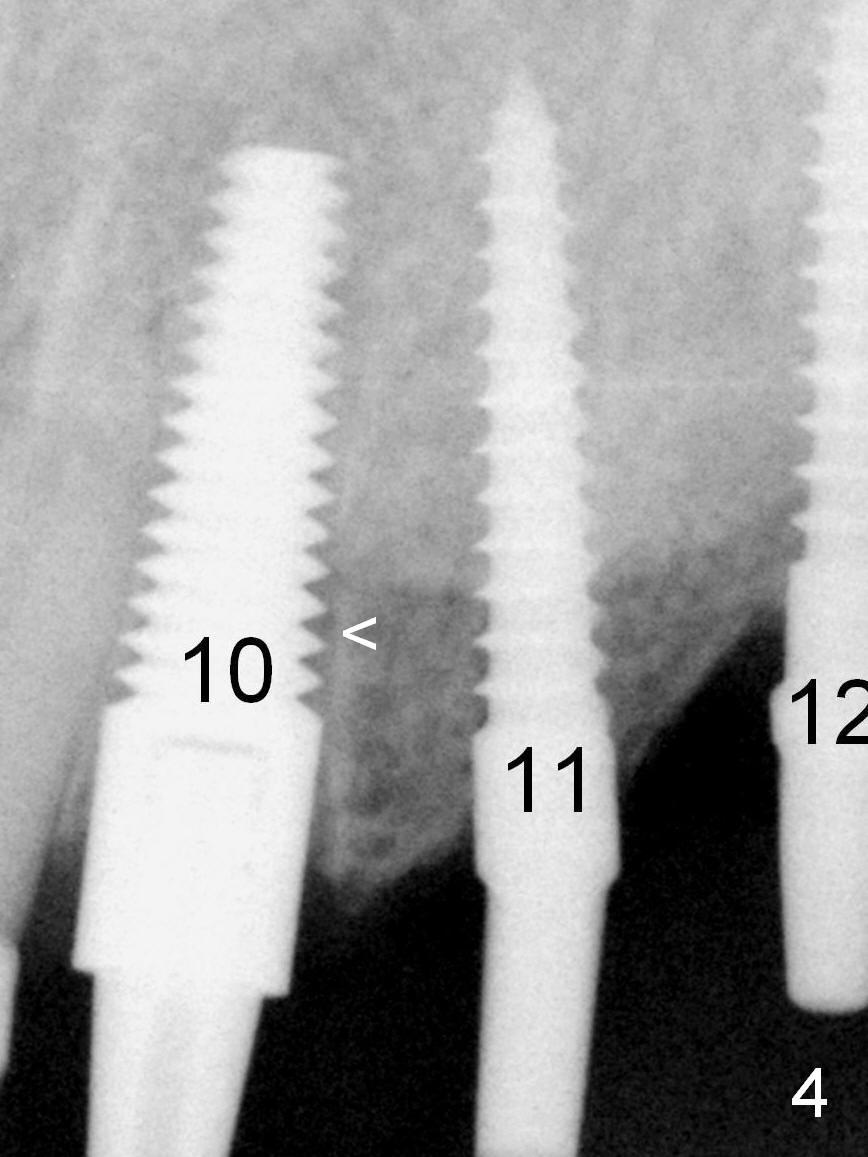

A 2-piece implant (4.5x17 mm tissue-level) is placed at #10 after extraction, while 1-piece implants are placed at #11 (3x17 mm (tissue-level, 15 °) and 12 (bone-level, 2.5x14 mm; Fig.4).

The patient returns for final restoration 3.5 months postop; it appears that the implants has osteointegrated (Fig.12). The bone has apparently grown into the threads of the implant, as compared to Fig.4 <). There is no crestal bone loss associated with these 3 implants.